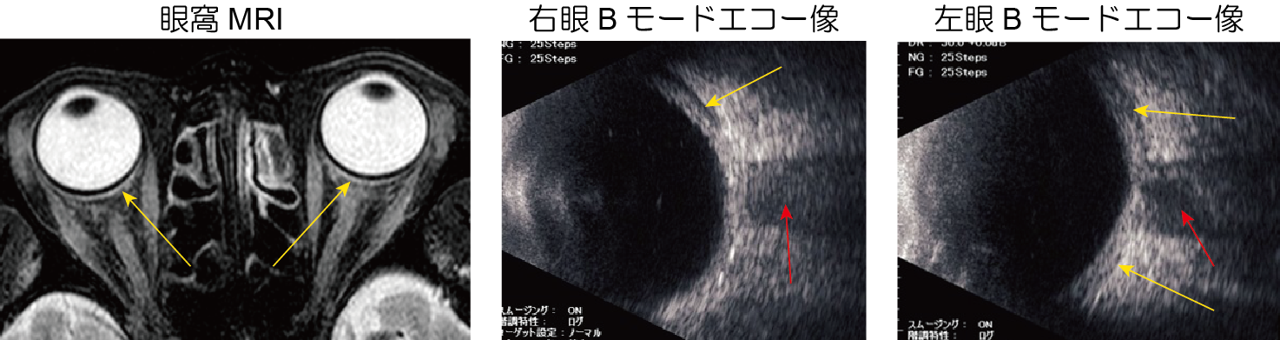

甲状腺眼症の斜視手術時期 複視を訴える甲状腺眼症に対する急性期治療はステロイドパルスや放射線外照射などの免疫抑制療法です。https://meisha.info/archives/2540しかし眼窩の炎症が沈静化した後、 ...